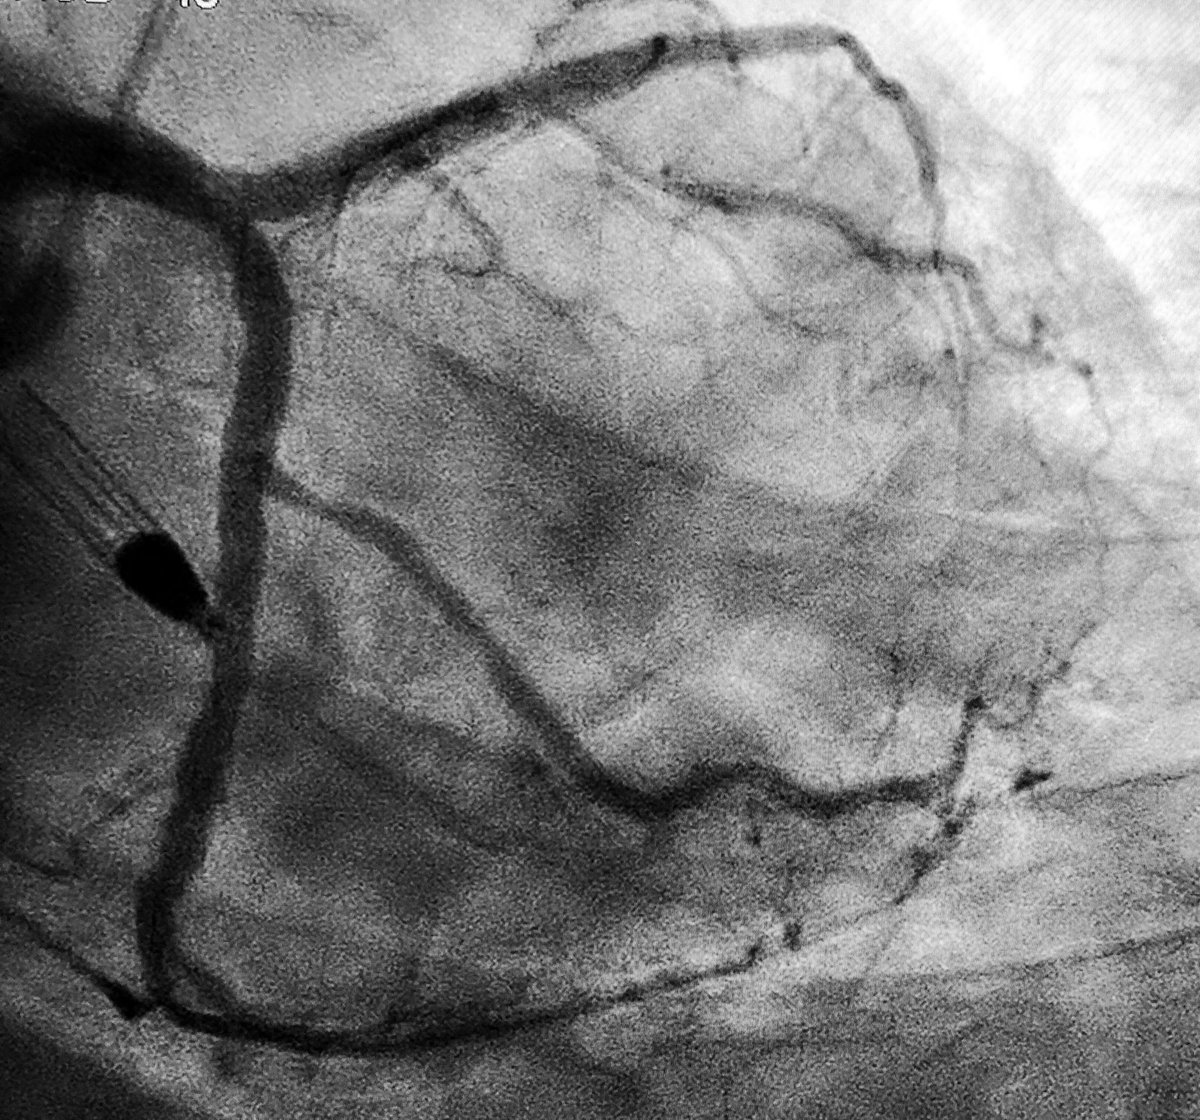

69yo lady with inferior STEMI

#radialfirst#cardiotwitter#cardioed#MedEd#accfit#somecvdpic.twitter.com/RUuklyv6noPrikaži ovu nit -